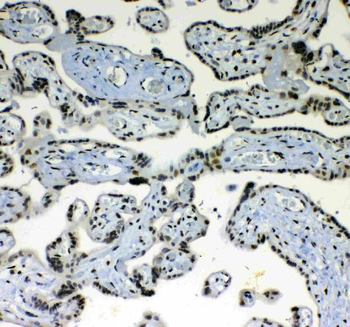

10 μg, 100 μg - Anti-HSD11B2 Antibody [orb316541]

IF, IHC, IHC-Fr, WB

Human, Mouse, Rat

Rabbit

Polyclonal

Unconjugated

10 μg, 100 μg - Anti-CD44 Antibody [orb402179]